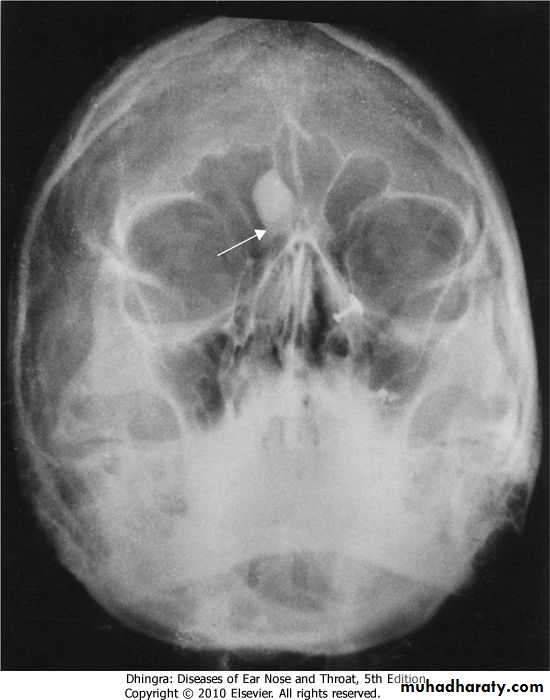

Frontal sinusitis and ethamoidal sinusitis can cause edema of the lids secondary to infection of the sinusesRADIOGRAPHIC FINDINGS:

OSTEOMA

15 to 40 yearsFrontal > Ethmoid > Maxillary

Slow-growing bone tumour &

often remains asymptomatic.

It can cause

obstruction of ostium

mucocele formation

pressure symptons

Rx :Local excision